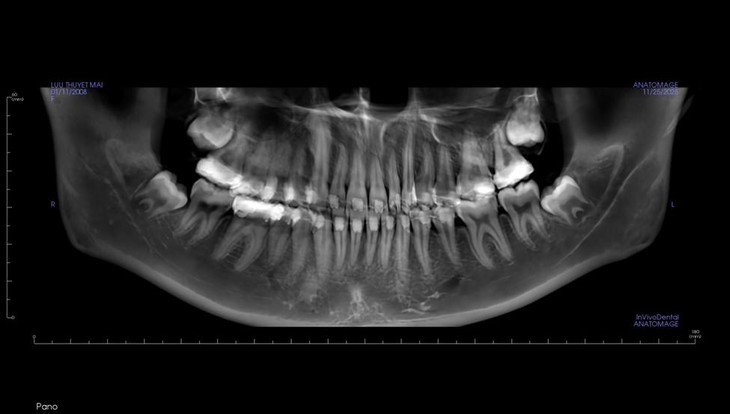

Trên phim X-quang, người bệnh có 4 răng khôn mọc lệch cần nhổ - Ảnh: BSCC

Vì khi mọc răng này, xương hàm đã ổn định, phần lớn trường hợp không còn đủ chỗ cho răng khôn phát triển bình thường. Hậu quả là răng có thể mọc lệch, ngầm gây viêm lợi, sâu răng kế cận, tiêu xương, hoặc đau kéo dài vùng góc hàm.